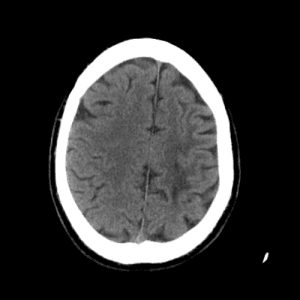

ACA and MCA territory infarct

Case #1